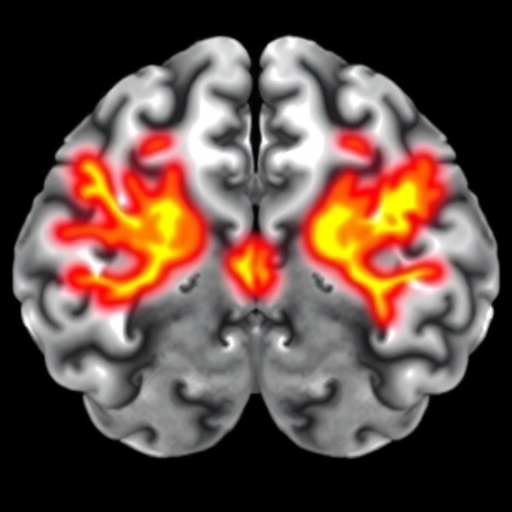

In a groundbreaking study recently published in Nature, researchers have uncovered critical insights into the mechanisms underpinning synapse loss and neuroinflammation in multiple sclerosis (MS). Traditionally viewed as a disease primarily targeting white matter, this new work reveals how focal white matter lesions can profoundly impact gray matter regions, driving synaptic degradation and sustained inflammatory responses. These findings mark a significant advance in understanding the pathophysiological cascade linking white matter damage to cortical dysfunction in neurodegenerative disorders and could reshape future therapeutic approaches.

Multiple sclerosis has long been characterized by focal demyelinating lesions predominantly affecting white matter tracts. However, emerging evidence indicates that gray matter pathology, including synaptic loss and microglia activation, plays a vital role in disease progression and clinical disability. Despite this, the mechanistic relationship between discrete white matter lesions and subsequent gray matter injury remained elusive. The current study addresses this knowledge gap by meticulously quantifying synaptic changes and neuroimmune activation following lesion induction within targeted neural circuits.

Ultimately, this comprehensive characterization of the synaptic and inflammatory landscape following focal white matter lesions redefines the conceptual framework of MS pathology. By linking discrete white matter injury to remote gray matter synapse loss through complement-dependent microglial mechanisms, the researchers open exciting avenues for targeted immunomodulatory and neurorestorative therapies.